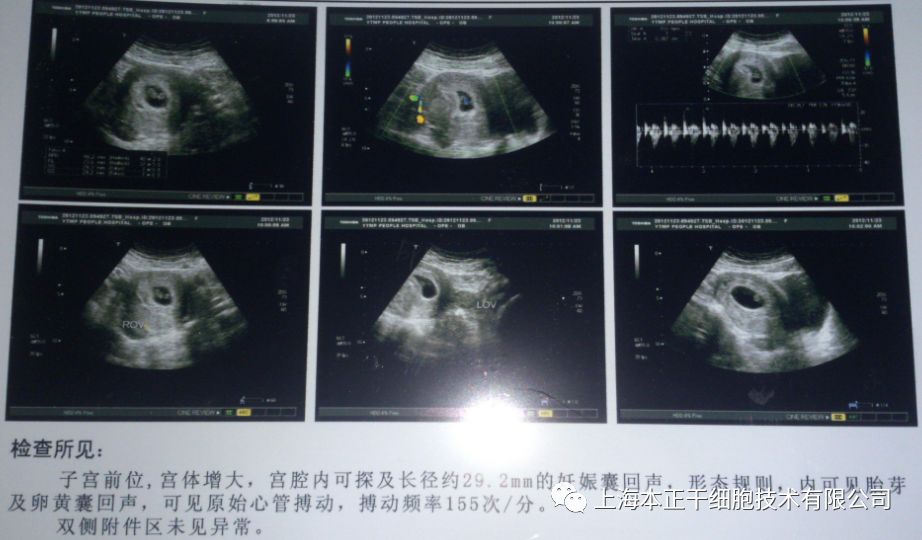

干细胞治疗方案:对患者刮宫后,在产生引导下用注射器经宫底及宫腔内注射入患者干细胞悬液,术后辅以阿司匹林和周期性激素治疗。超声检查结果显示患者术后子宫内膜再生较好,并且,患者通过体外受精(in vitro fertilization,IVF)成功怀孕,随访至妊娠第八周胎儿生长良好。

图5:胚胎移植后孕囊、卵黄囊、胚胎极及β-HCG阳性试验

图6:可见胚胎有心脏活动

图7:3D扫描8周的胎儿

2013年,Zhao等针对反复流产导致的难治型IUA病人,常规治疗无效后,行宫腔粘连分解术,术后利用间充质干细胞联合雌激素人工周期治疗,使其成功受孕。